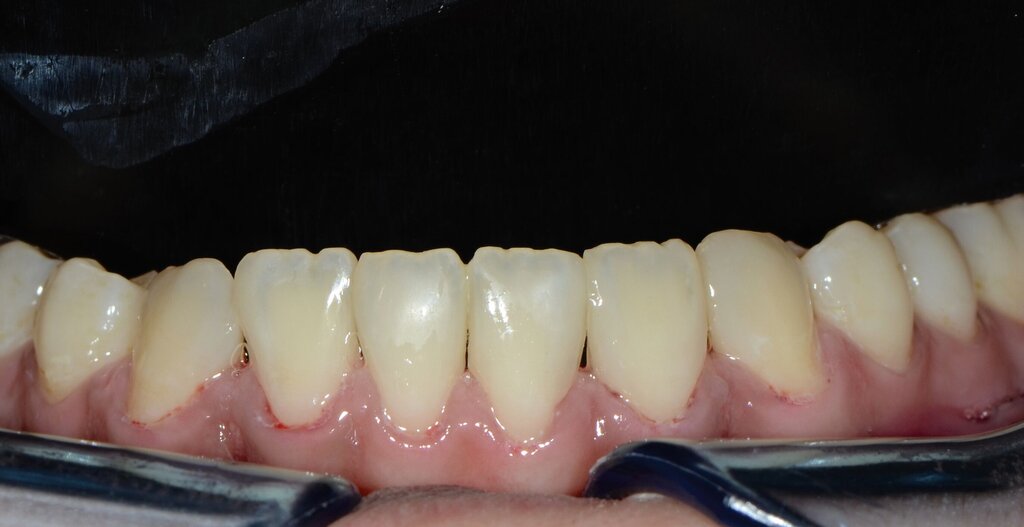

... in der Restaurationsklasse V

Direkte Klasse-V-Komposit-Restaurationen zeigten in Langzeitbeobachtungen (zwölf Monate bis 13 Jahre) hohe Überlebensraten und niedrige jährliche Ausfallraten [Schwendicke et al., 2016; Bezerra et al., 2020; Boing et al., 2018; Hayes et al., 2016; Heintze et al., 2010; Mahn et al., 2015; Meyer-Lueckel et al., 2019; Peumans et al., 2005; Peumans et al., 2014; Santos et al., 2014]. In allen Übersichten wurden Glasionomerzemente oder modifizierte Glasionomerzemente als häufigste Vergleichsmaterialien verwendet. Die Retention von Klasse-V-Restaurationen war ein zentraler Aspekt, wobei Glasionomerzemente tendenziell besser abschnitten. Allerdings erwies sich das Adhäsivprotokoll als entscheidend für die Retention von Kompositen, insbesondere für 3-Schritt-Etch-and-Rinse-, 2-Schritt-Self-Etch- und Universaladhäsive, wodurch eine vergleichbare Langzeitretention mit Glasionomerzementen erreicht wurde. Bei anderen klinischen Qualitätsparametern wie Randanpassung, anatomische Form, Oberflächentextur und Sekundärkaries zeigten Komposite ähnliche Ergebnisse wie Glasionomerzemente. In der Ästhetik sind sie den Glasionomerzementen überlegen (Abbildung 4).